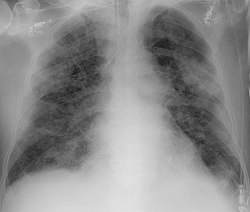

Imaging[edit | edit source]

Chest CT scans may be helpful to diagnose COVID-19 in individuals with a high clinical suspicion of infection but are not recommended for routine screening.[93][105] Bilateral multilobar ground-glass opacities with a peripheral, asymmetric, and posterior distribution are common in early infection.[93][106] Subpleural dominance, crazy paving (lobular septal thickening with variable alveolar filling), and consolidation may appear as the disease progresses.[93][107] Characteristic imaging features on chest radiographs and computed tomography (CT) of people who are symptomatic include asymmetric peripheral ground-glass opacities without pleural effusions.[108]

Many groups have created COVID-19 datasets that include imagery such as the Italian Radiological Society which has compiled an international online database of imaging findings for confirmed cases.[109] Due to overlap with other infections such as adenovirus, imaging without confirmation by rRT-PCR is of limited specificity in identifying COVID-19.[108] A large study in China compared chest CT results to PCR and demonstrated that though imaging is less specific for the infection, it is faster and more sensitive.[92]